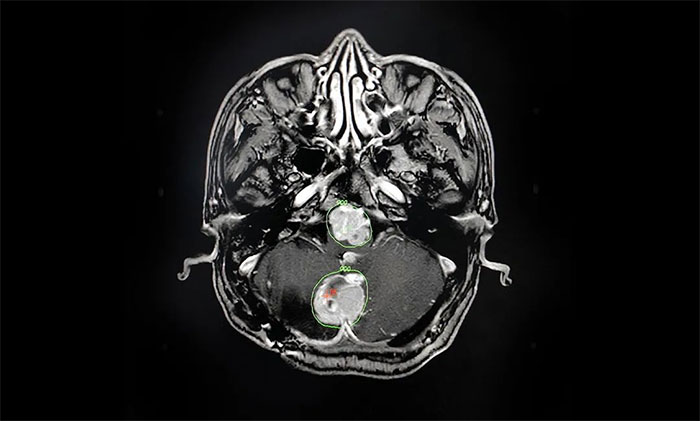

▲ 科学制定伽玛刀治疗计划

经过详细论证,拟定好个性化的治疗方案后,陈琦主任将治疗过程为患者及家属进行了详细说明,并明确告知过程中可能存在的风险。在取得家属一致同意、签字确认后,他立即投入术前的准备工作中。